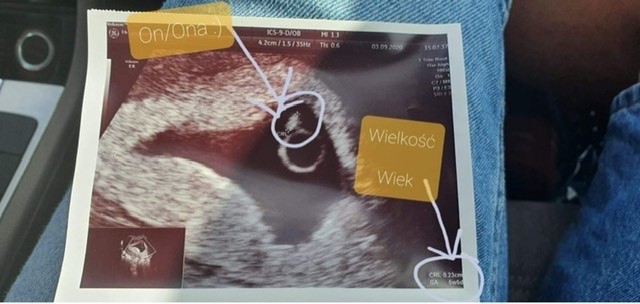

Malutki kropeczekUSG z pierwszej wizyty

No właśnie nie.. byłam dzisiaj na USG bo plamienia coraz większe.. okazało się że przez 3 dni pęcherzyk nie urósł wgl.. powoli tracę nadziejęMoj mąż jakiś robił opis zdjęcia. A jak tam u Ciebie z plamieniem ? Skończyło się. ?